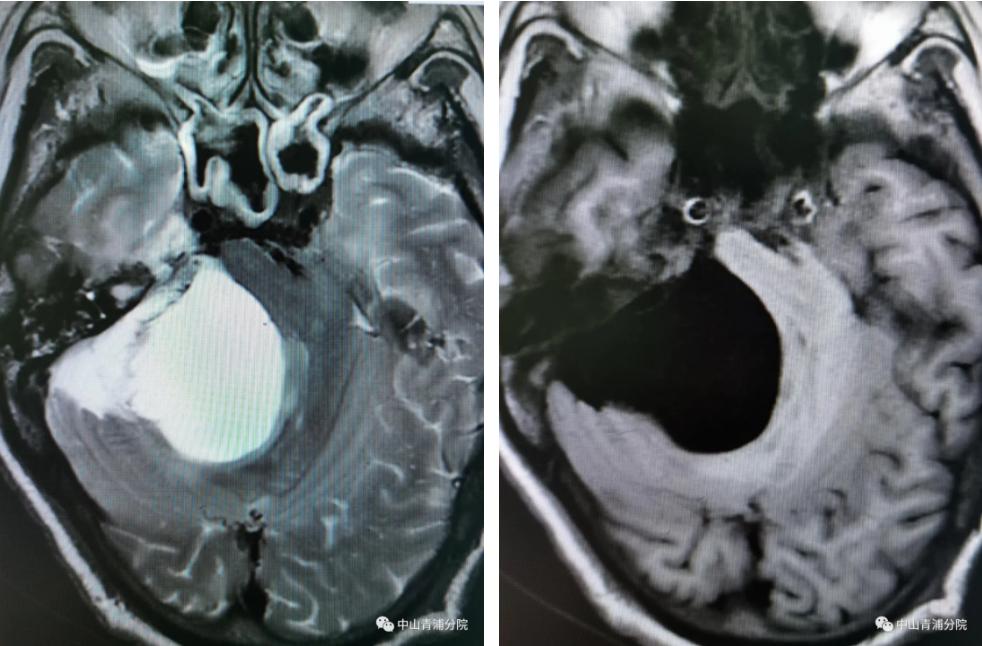

入院后,头颅磁共振检查提示右侧桥小脑脚低密度病灶,最大直径5cm,脑干受压明显。神经内科吴卫文主任团队开展了病例讨论,并与家属进行了充分的沟通,考虑到颅内占位脑干受压明显可能危及生命,建议提前干预和治疗,家属同意后,请神经外科会诊。

(术前头颅MRI) (术前头颅MRI)